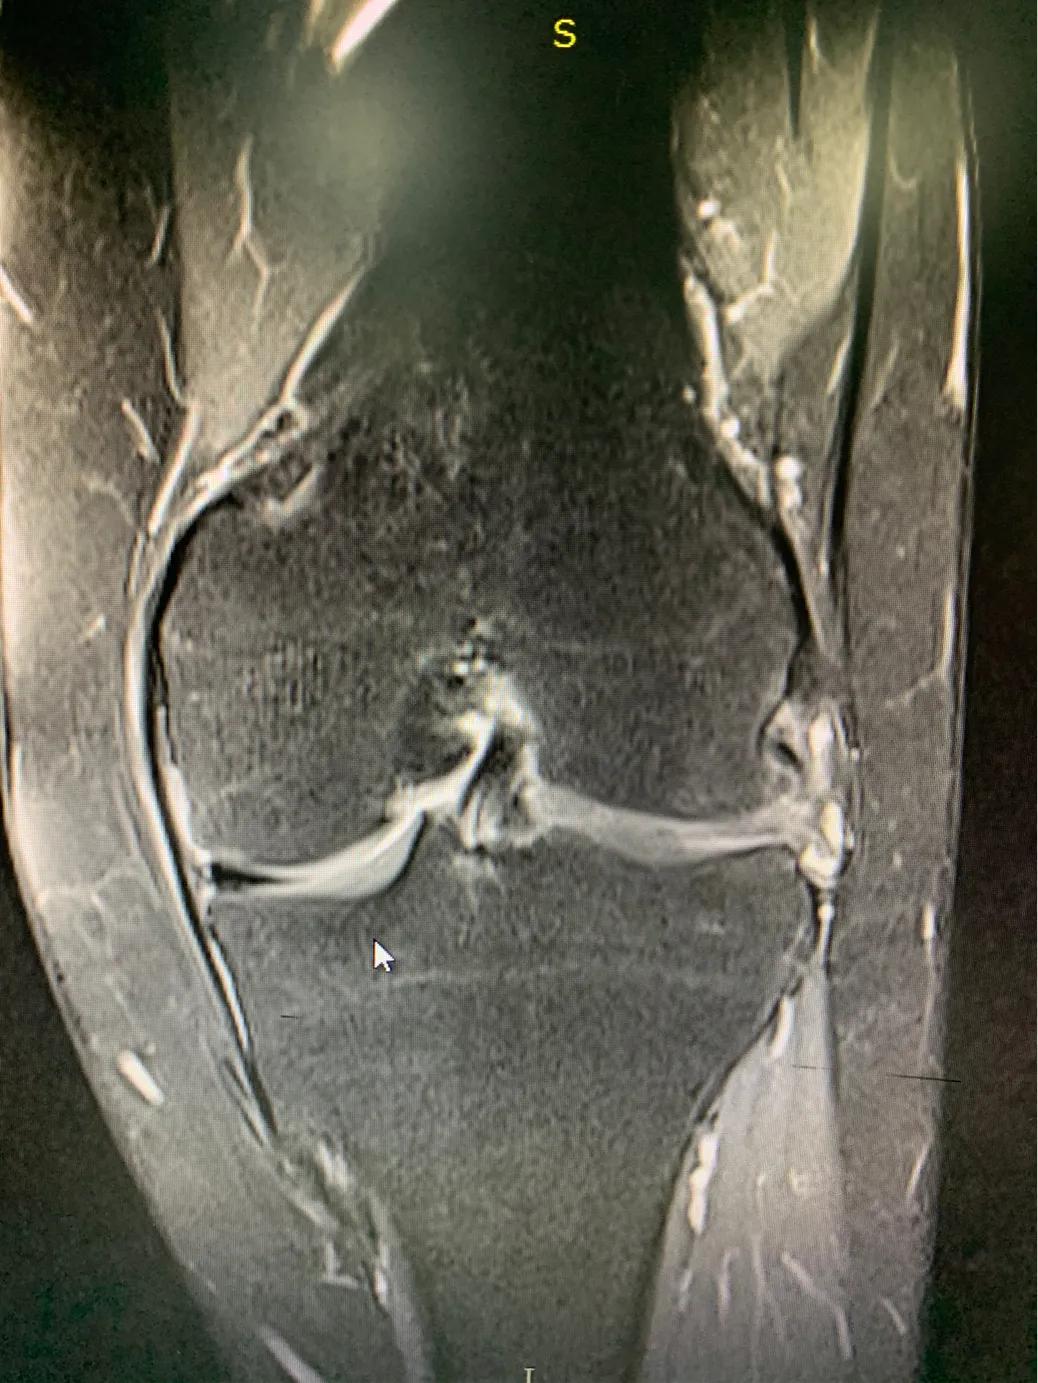

半月板损伤的磁共振